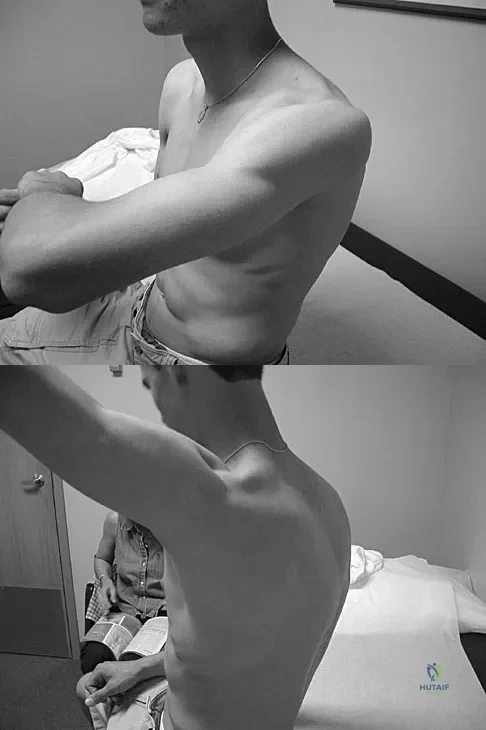

A 22-year-old woman has had progressive upper extremity weakness for the past several years. History reveals no pain in her neck or shoulders. Examination reveals scapular winging of both shoulders and weakness in external rotation. She can abduct to only 120 degrees bilaterally, and there is mild supraspinatus weakness. She is otherwise neurologically intact with normal sensation and reflexes; however, she has difficulty whistling. A clinical photograph is shown in Figure 14. What is the most likely diagnosis?

Explanation